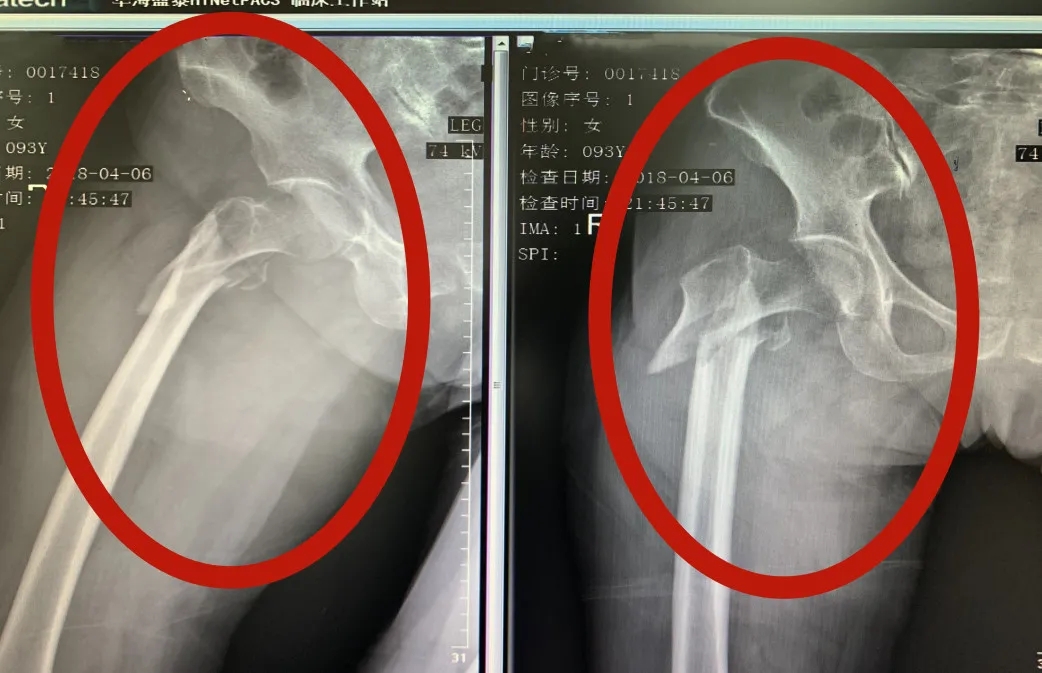

据了解,三年前唐奶奶因不慎摔倒,导致左股骨转子间骨折,遂来到河池市人民医院创伤手外科接受微创PFNA内固定术,术后恢复效果佳,已能正常行走。2021年12月26日,唐奶奶在家又不慎摔倒,出现左上臂疼痛、畸形、不能屈伸活动,剧烈的疼痛使她难以起床,生活无法自理。唐奶奶的子女们回想起上一次手术后的良好效果,于是,他们再次来到河池市人民医院创伤手外科请求帮助。创伤手外科副主任姚泓成得知情况后,仔细查看检查结果,诊断为左肱骨干骨折,考虑到老人已经96岁高龄,再加上患有多年的高血压、冠心病,姚泓成副主任组织医疗团队第一时间展开讨论,最终决定为老人做骨折手术。

唐奶奶三年前X线术前检查结果VS术后检查结果